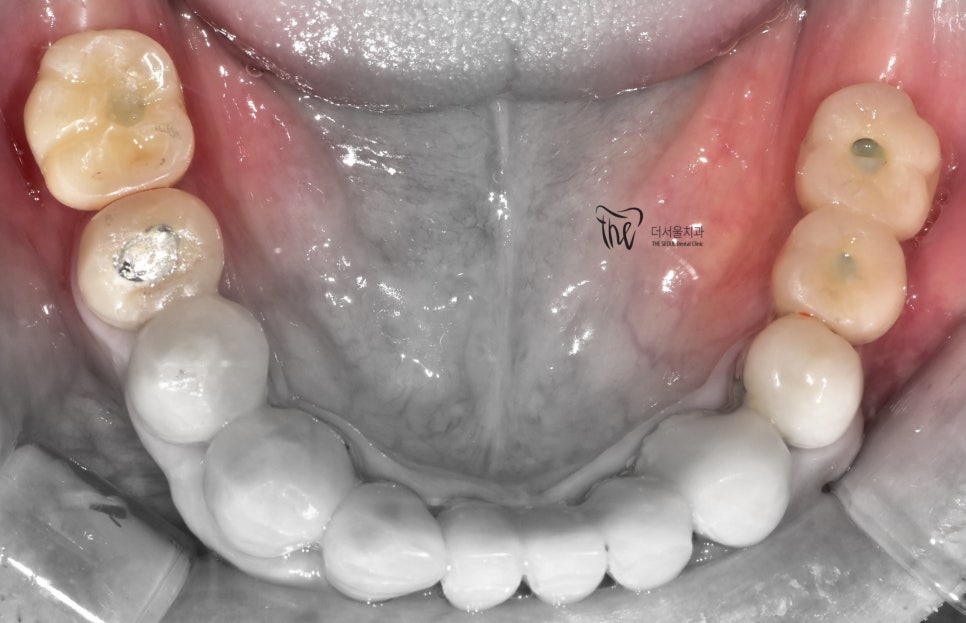

자, 이렇게 치과 에서 없던 치아를 다시

만들어드렸습니다.

앞서 치아 정출에 관련되어서 말씀드렸죠?

사실 이 분은 임플란트 4개 가량을 심는 것이

적합한 상황이였습니다.

사진을 기준으로, 좌측의 경우에는

지르코니아 크라운이 연결되면서

대합치의 정출을 막을 수 있는 위치에

배치가 되었으나

우측의 경우에는 맨 끝에 있는 후방치는

그렇지 않은것을 볼 수 있습니다.

다만, 이렇게 치료를 해드렸어도

식사를 하는데 지장은 없습니다.

오히려, 기존 식사를 거의 앞니로만

하셨던 상황이였기 때문에 없던 어금니가

만들어져서 더 행복해졌다는 얘길 하시네요.^^